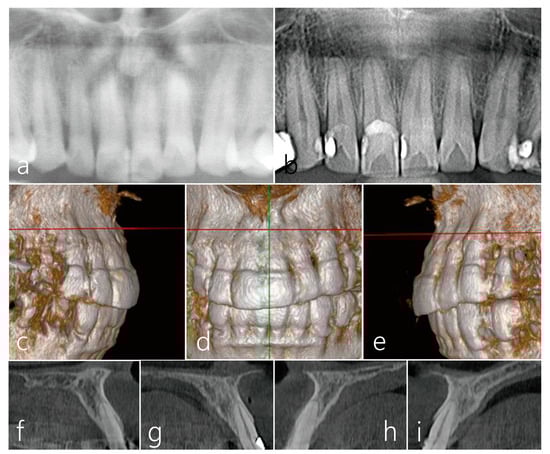

2. Case Presentation

Surgical Procedure

3. Results